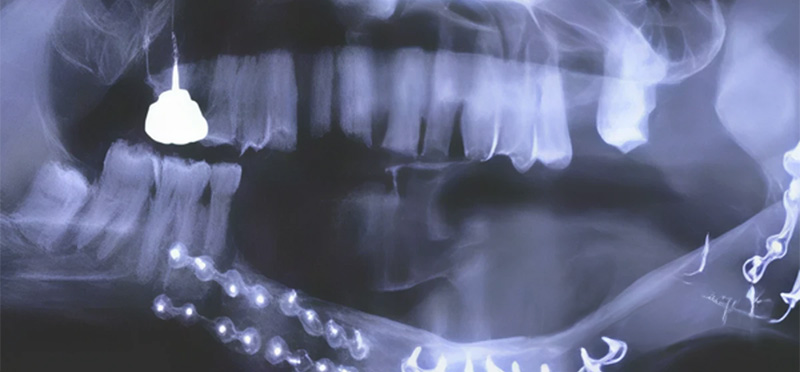

Fig. 01.

Fig. 03 : reconstruction mandibulaire par greffe libre de péroné.

Fig. 03 : reconstruction mandibulaire par greffe libre de péroné.

La chirurgie aboutit à des pertes de substances nécessitant des réparations plus ou moins importantes. Les petites pertes de substance, comme pour une tumeur T1, ne nécessiteront pas d’apport tissulaire. A contrario, les grandes pertes feront appel à des lambeaux pédiculés comme le grand pectoral, le grand dorsal ou des lambeaux libres tels que des greffes de péroné pour la reconstruction mandibulaire. Ces lambeaux assurant la survie du patient, la restauration des fonctions et l’esthétique.